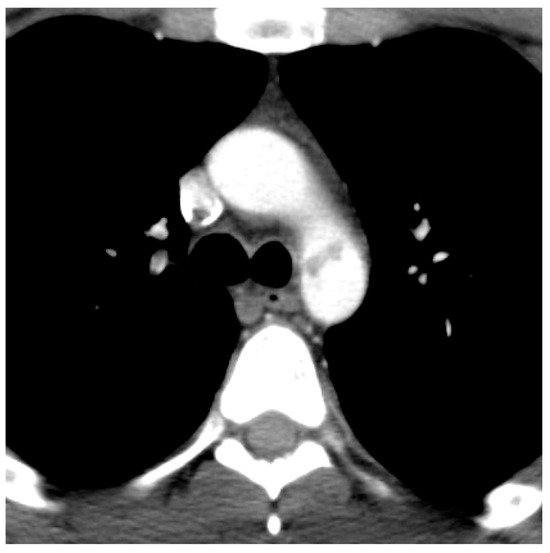

| 1 (intimal tear) | 4 (11%) |